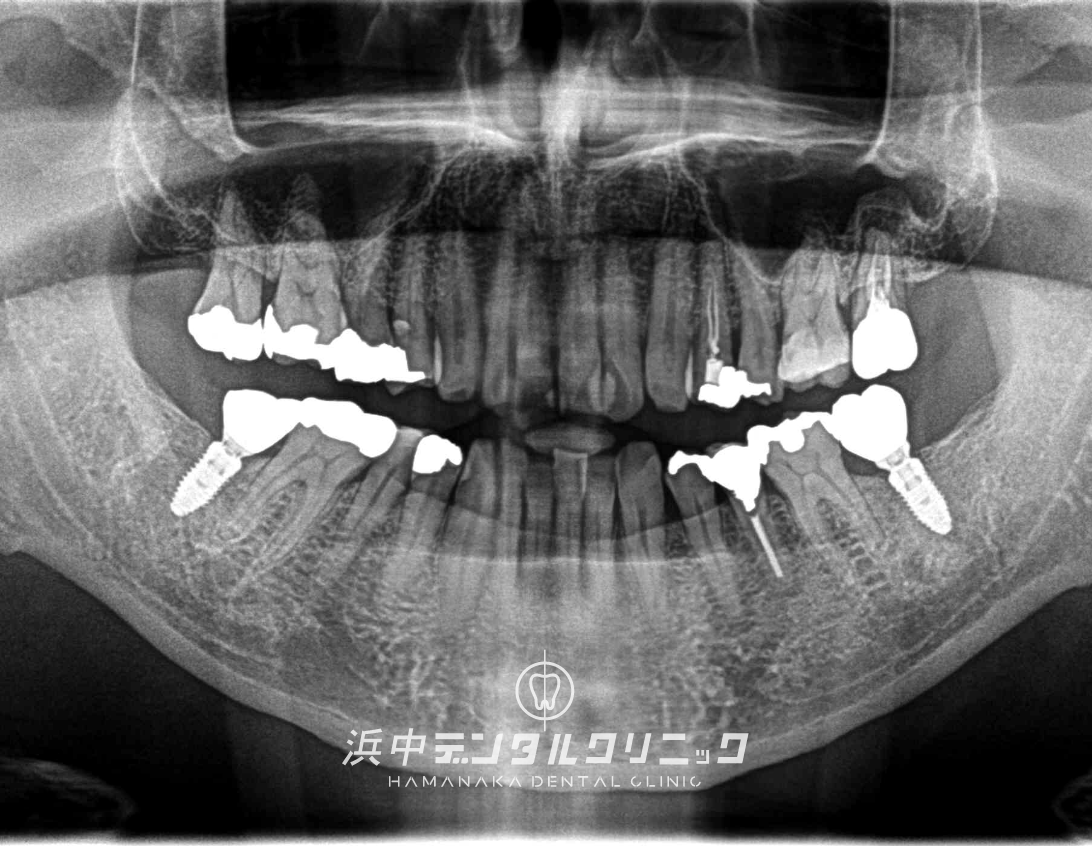

BEFORE

AFTER

患者様の主訴

下の両方の奥歯が割れたので噛めるようにしたい。

診断結果

日常的に強い歯ぎしりをしてる患者様で下顎左右の7番目の歯が歯根破折をしてました。

治療内容

下顎左右両側の7番目の歯を抜歯後にインプラントを埋入して仮歯を経て最終上部構造(ジルコニアセラミック)をスクリュー固定しました。

治療後経過

インプラント治療終了後から約3年経過していますが全く問題なく経過良好です。

| 治療期間 | 約7ヶ月 |

|---|---|

| 治療にかかった費用 | インプラント体(フィスクチャー308,000円)×2本 +インプラント土台(アバットメント77,000円)×2本 +インプラント人工歯(上部構造ジルコニアセラミック165,000円)×2本 +静脈内鎮静麻酔77,000円+仮歯代22,000円×2本分 +サージカルステント55,000円 =合計1,276,000円 |

| リスク副作用 | インプラントは入れたら終わりではなく、きちんとメンテナンスしないと歯周病になることもあるので、定期的にクリーニングや噛み合わせの調整が必要です。 |